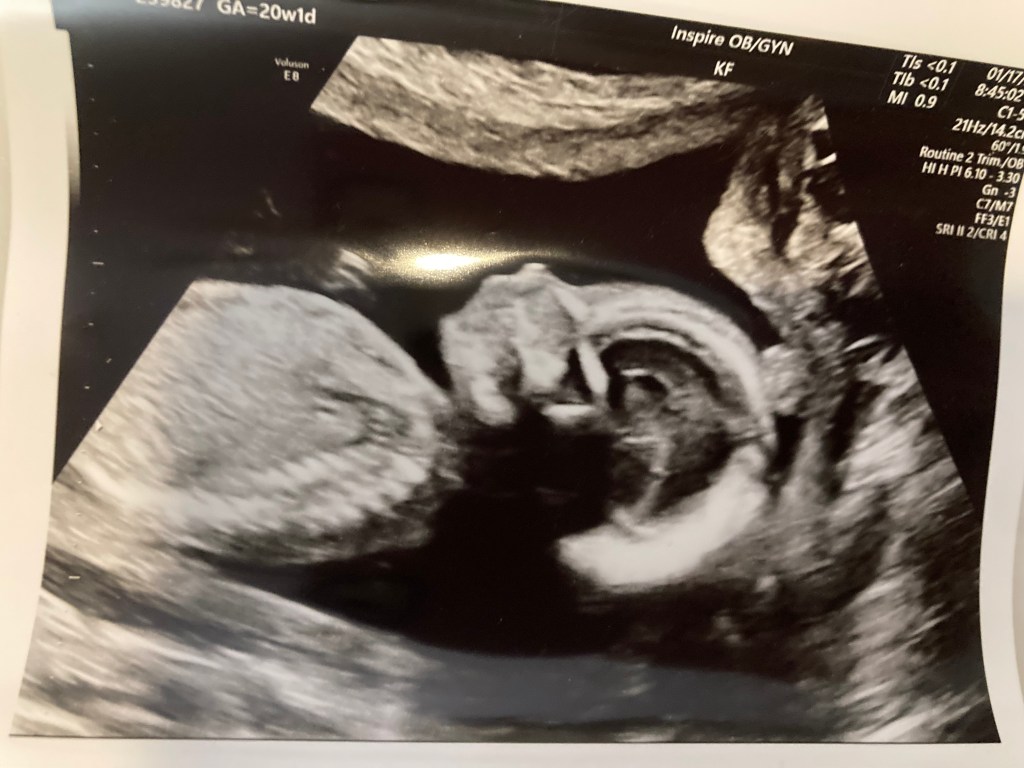

We are so excited for this new year the Lord has given us! It is going to be a crazy year for our family but we can’t wait to see all that the Lord is going to do. First of all, we are so excited to announce that God has blessed us with our third daughter arriving in late May or early June. In March we will be going back to Argentina and we are preparing for our first church plant later this year.

- Healthy delivery of our baby girl.